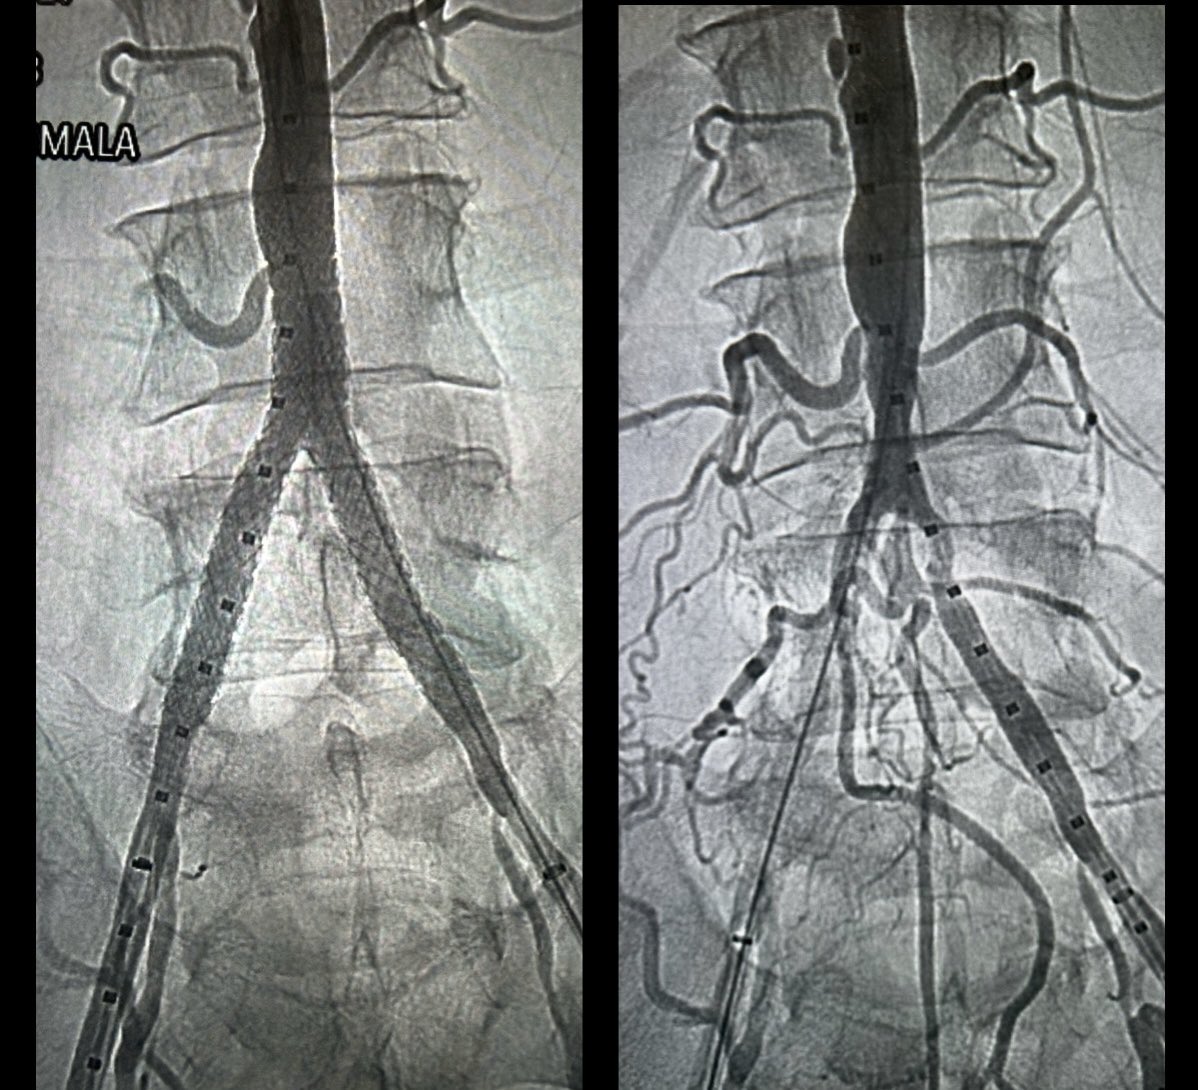

Partial disassembly at the junction to expose the internal stiff wire lets you manually control the lever and free a stuck Perclose footplate—turning a stressful moment into a controlled one. Practical, reproducible, and worth remembering.